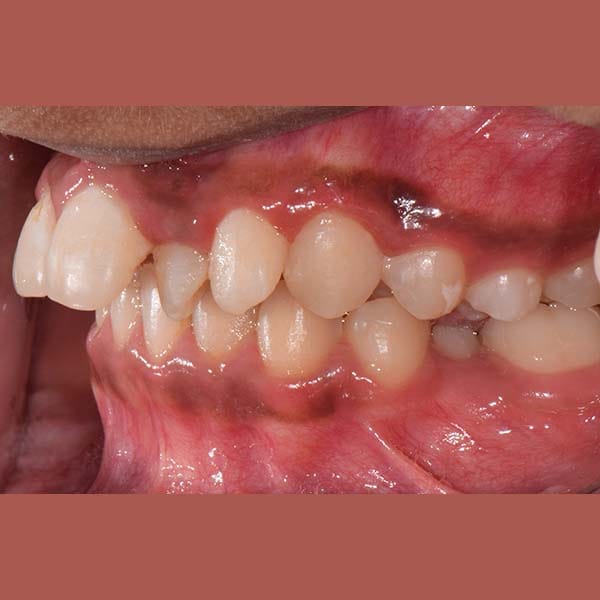

قبل

ابتسامة جميلة جدا